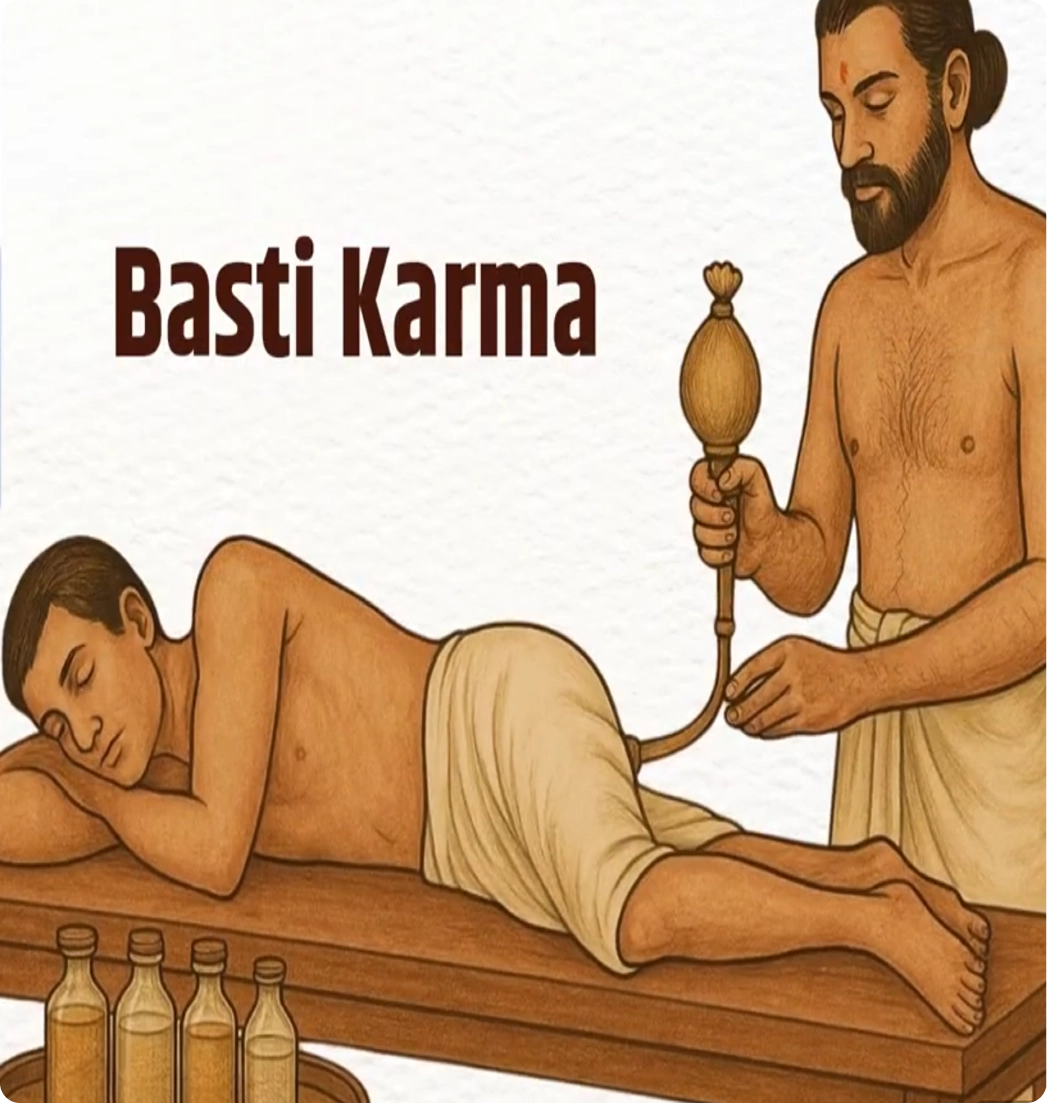

Basti

-

What Is This Therapy

Basti is an Ayurvedic therapy that uses herbal oil or decoction enemas to cleanse and nourish the colon.

-

How It Works

Medicinal oils are gently introduced into the colon to remove toxins and lubricate internal tissues.

-

Why This Therapy

Two main basti therapies include Niruha Basti (Asthapana Basti) and Anuvasana Basti to clean the colon, which is the root of many imbalances; cleansing it supports gut health, immunity, and mental clarity.

-

Benefits

Improved digestion, reduced inflammation, balanced Vata energy, and overall body rejuvenation.

Watch Video